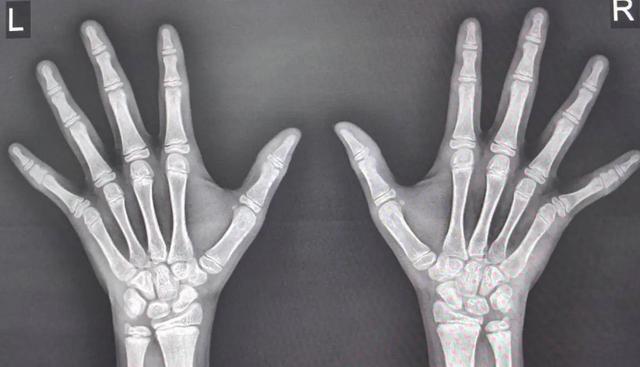

AI读片5分钟出结果,11岁男孩骨龄13岁半,生长板只剩一条缝。

以前人工读片误差大,现在AI模型练了30万张X光,误差缩到0.2岁,一眼能看出孩子还剩几年可长。

关键节点:女孩骨龄14岁、男孩16岁,生长板基本下班,再补啥都晚了。